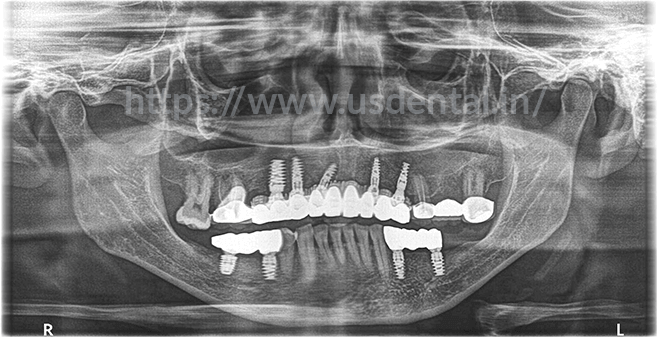

After proper planning to mockup cast, cbct and clinical conditions, we advised patient 4 to 5 implants in the upper anterior region of the jaw and two implants on both side posterior region of the lower jaw. Implant placement was done with the help of computer guided surgery. The provisional bridge was given to the patient for three to four-month time. As advised, the patient revisited to our

dental clinic in Ahmedabad after a time period of 4 months. By that time, the patient was having lower removable dentures and an upper fixed bridge. After 4 months, the second stage of implants was done and multiunit with healing cap were placed. After tissue settled down, the final implant impression was taken for fabrication of a final prosthesis.

After proper planning to mockup cast, cbct and clinical conditions, we advised patient 4 to 5 implants in the upper anterior region of the jaw and two implants on both side posterior region of the lower jaw. Implant placement was done with the help of computer guided surgery. The provisional bridge was given to the patient for three to four-month time. As advised, the patient revisited to our dental clinic in Ahmedabad after a time period of 4 months. By that time, the patient was having lower removable dentures and an upper fixed bridge. After 4 months, the second stage of implants was done and multiunit with healing cap were placed. After tissue settled down, the final implant impression was taken for fabrication of a final prosthesis.

After proper planning to mockup cast, cbct and clinical conditions, we advised patient 4 to 5 implants in the upper anterior region of the jaw and two implants on both side posterior region of the lower jaw. Implant placement was done with the help of computer guided surgery. The provisional bridge was given to the patient for three to four-month time. As advised, the patient revisited to our dental clinic in Ahmedabad after a time period of 4 months. By that time, the patient was having lower removable dentures and an upper fixed bridge. After 4 months, the second stage of implants was done and multiunit with healing cap were placed. After tissue settled down, the final implant impression was taken for fabrication of a final prosthesis.